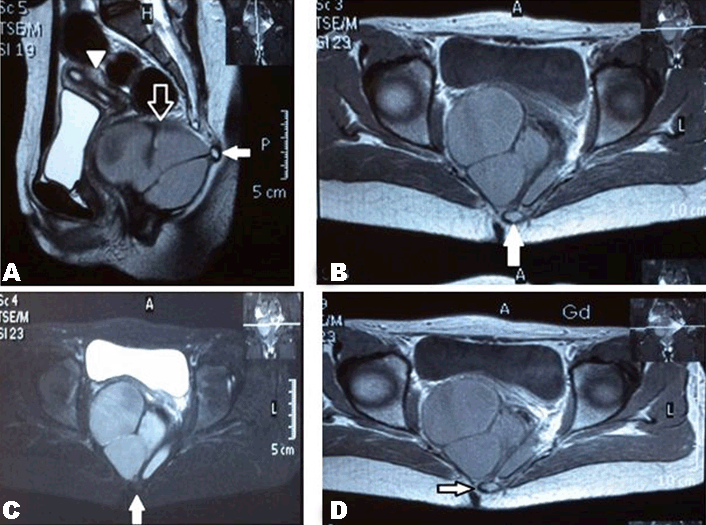

Case 1 History and Examination The patient had a history of a small bulge in the perineum on the right side and a small sinus just below her coccyx during her lifetime. She had no leg pain or paresthesias, no difficulties in urination or defecation, no weight loss, and was able to walk with no difficulties. The patient had an uneventful medical and surgical history with a negative parental consanguinity and a negative family history for same. No irregularities were marked in the menstrual cycle since her menarche at 12 years. In the last two years, she had a decrease in the duration of bleeding (from seven to three days) but with a normal amount of flow. On physical examination, lower limbs revealed normal muscle tone and power, intact sensation, normal reflexes and intact sphincters and rectal mucosa, which was further confirmed by digital rectal examination. A large cystic mass was observed pushing the rectum posteriorly with the mucous membrane moving over it. Diagnostic evaluation Surgery The wound was packed with gauze flavored with iodine and left for secondary healing to take place with regular dressing till 21 days. Histopathological examination Microscopically, the sections showed mature respiratory mucosa, squamous epithelium, mucinous gland and glial elements associated with fibrofatty tissue, bundles of nerve fibers and smooth muscle. It also contained coccygeal bone. The diagnosis was mature cystic teratoma. Outcome Magnetic resonance imaging of pelvis and lumbosacral region revealed it to be free of mass with the restoration of the position of the rectum, bladder and the site of coccygectomy (Figure 4). Case 2 History and Examination The patient had a history of small sinus without discharge below the coccyx. She had no leg pain or paresthesias, no difficulties in urination or defecation, no weight loss and no walking difficulties. The patient had uneventful medical and surgical history with a negative parental consanguinity and a negative family history for same. Her menstrual cycle was regular, with no change in the amount or duration. Her menarche started at 15 years. Physical examination of lower limbs revealed normal muscle tone and power, intact sensation, normal reflexes, intact anal sphincter and normal rectal mucosa, which was further confirmed by digital rectal examination. A cystic mass was found to be pushing on the rectum posteriorly; the mucous membrane was found moving over it. Diagnostic evaluation Magnetic resonance imaging of pelvis and lumbosacral region revealed a large (17×15×10 cm) lobulated outline, hyperintense signal on T1- and T2- with a small (2×10 mm) fatty component near the coccyx, arising from the anterior of lower sacrum and extending posteriorly to the gluteal region more on the right side below the coccyx to the pelvis. It caused displacement of the rectum posterolaterally and uterus and urinary bladder anteriorly. No enhancement was seen after gadolinium contrast (Figure 5). Surgery Histopathological examination A small cyst lined by ciliated epithelial cells was found on one side and squamous epithelial cells on the other, with enteric glandular component seen in the wall of the main cyst. A piece of the bone was present. The diagnosis was chronically inflamed pilonidal sinus with mature cystic teratoma. Outcome | ||||||